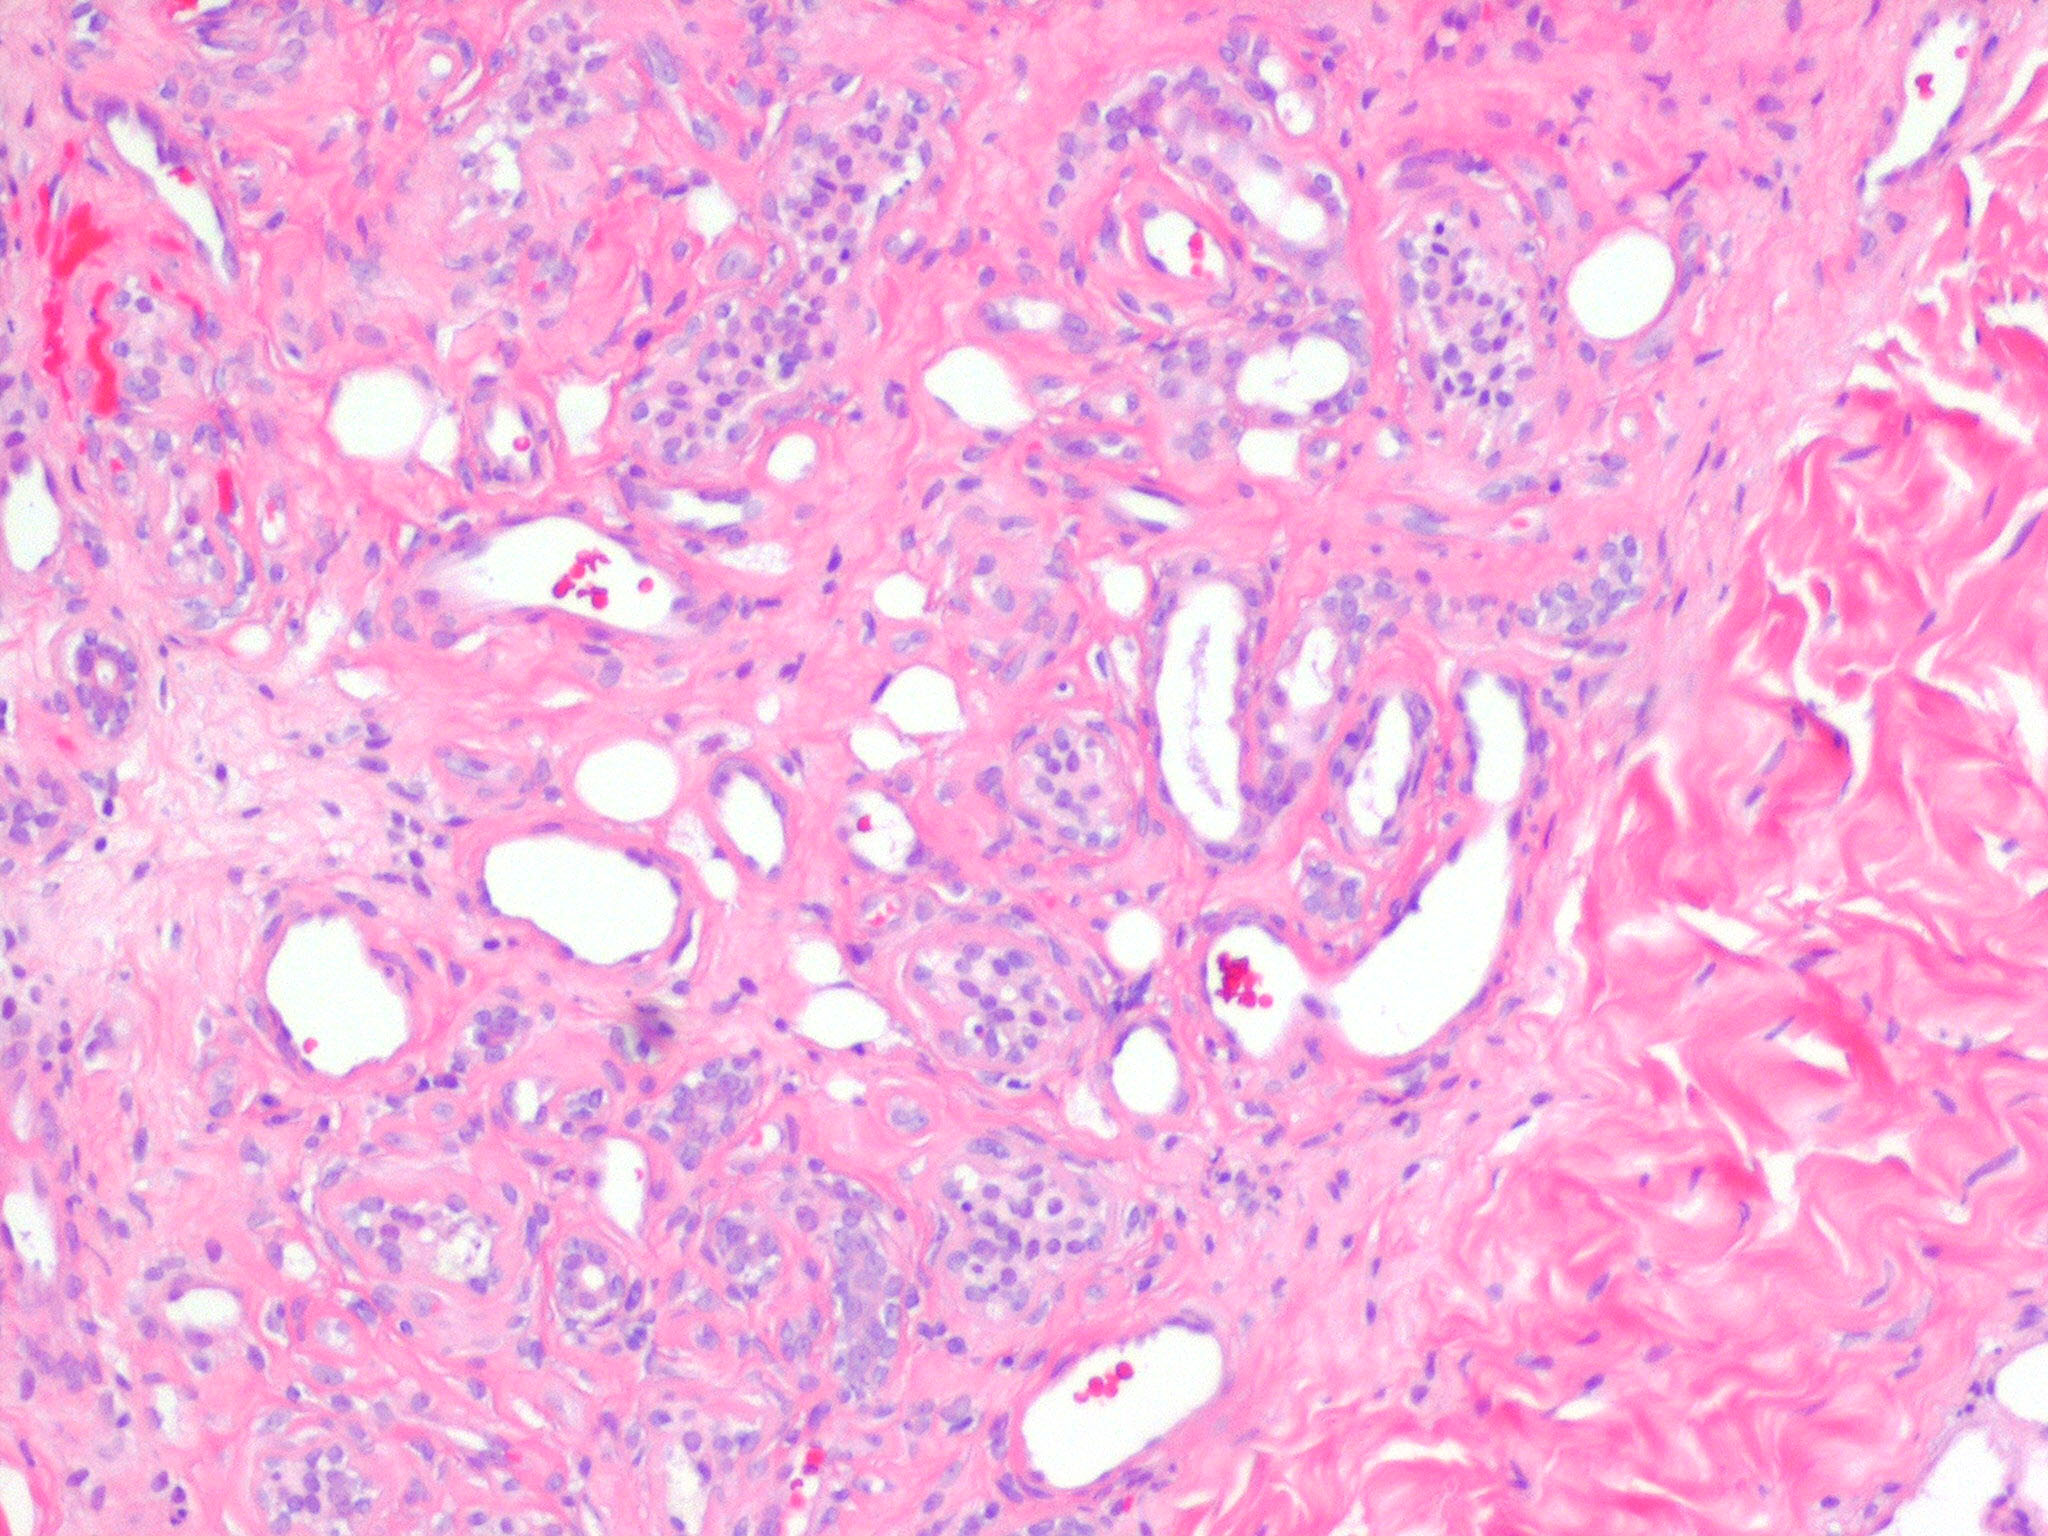

Eccrine angiomatous hamartoma = ورم عجائبي وعائي وناتح

OLYMPUS DIGITAL CAMERA